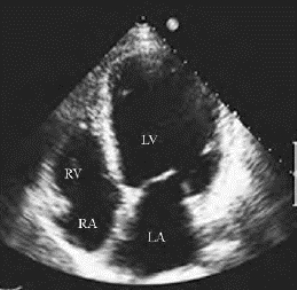

(1)各心腔扩大,左心型者以左房室扩大明显(图20-1),右心型者以右房室扩大明显,全心型者各心腔皆明显扩大。射血分值明显减低。

图20-1 扩张型心肌病声像图

图为心尖四腔观,显示左室、左房显著扩大